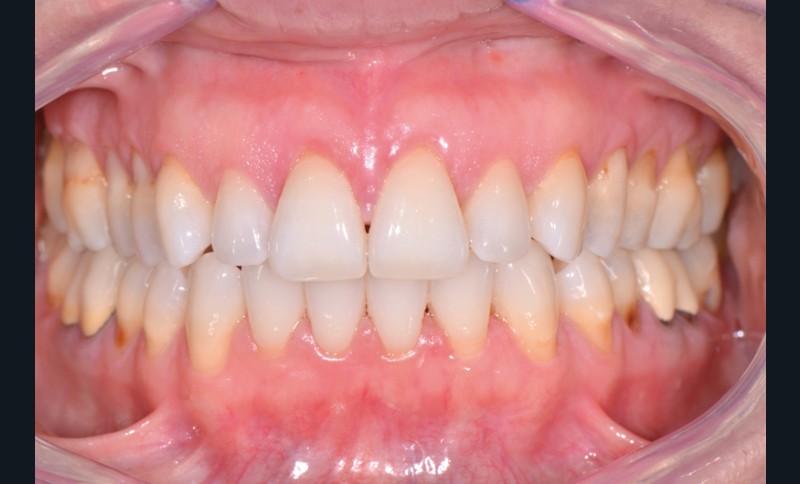

L’examen clinique révèle un biotype de type III et IV de Maynard et Wilson [1], dans les secteurs latéraux, une inflammation modérée en corrélation avec des dépôts supra-gingivaux et des restaurations débordantes, l’absence de poches parodontales, des pertes papillaires de classe I de Nordland et Tarnow [2] et des récessions gingivales associées à des lésions cervicales d’usure non carieuses et carieuses (35/45) majoritairement comblées par des restaurations en résine composite (fig. 1).